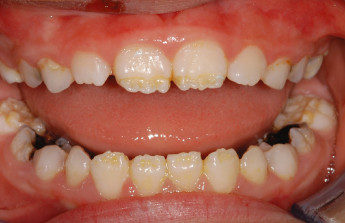

Enamel is the hard, protective outer layer of your teeth. Enamel hypoplasia is a defect of the enamel that only occurs while teeth are still developing. Still, it can affect both baby teeth and permanent teeth. The condition results in thin enamel, which makes your teeth vulnerable to dental decay.

The visual signs of enamel hypoplasia include white spots, pits, and grooves on the outer surface of the teeth.

pits, tiny groves, depressions, and fissures

white spots

yellowish-brown stains (where the underlying layer of dentin is exposed)

sensitivity to heat and cold

lack of tooth contact, irregular wearing of teeth

susceptibility to acids in food and drink

retention of harmful bacteria

increased vulnerability to tooth decay and cavities.

Defective enamel development can be the result of an inherited condition called amelogenesis imperfecta, or congenital enamel hypoplasia, which is estimated to affect about 1 in 14,000 people in the United States. This condition can also cause unusually small teeth and a variety of dental problems. Congenital enamel hypoplasia can happen alone or as part of a syndrome affecting other parts of the body.